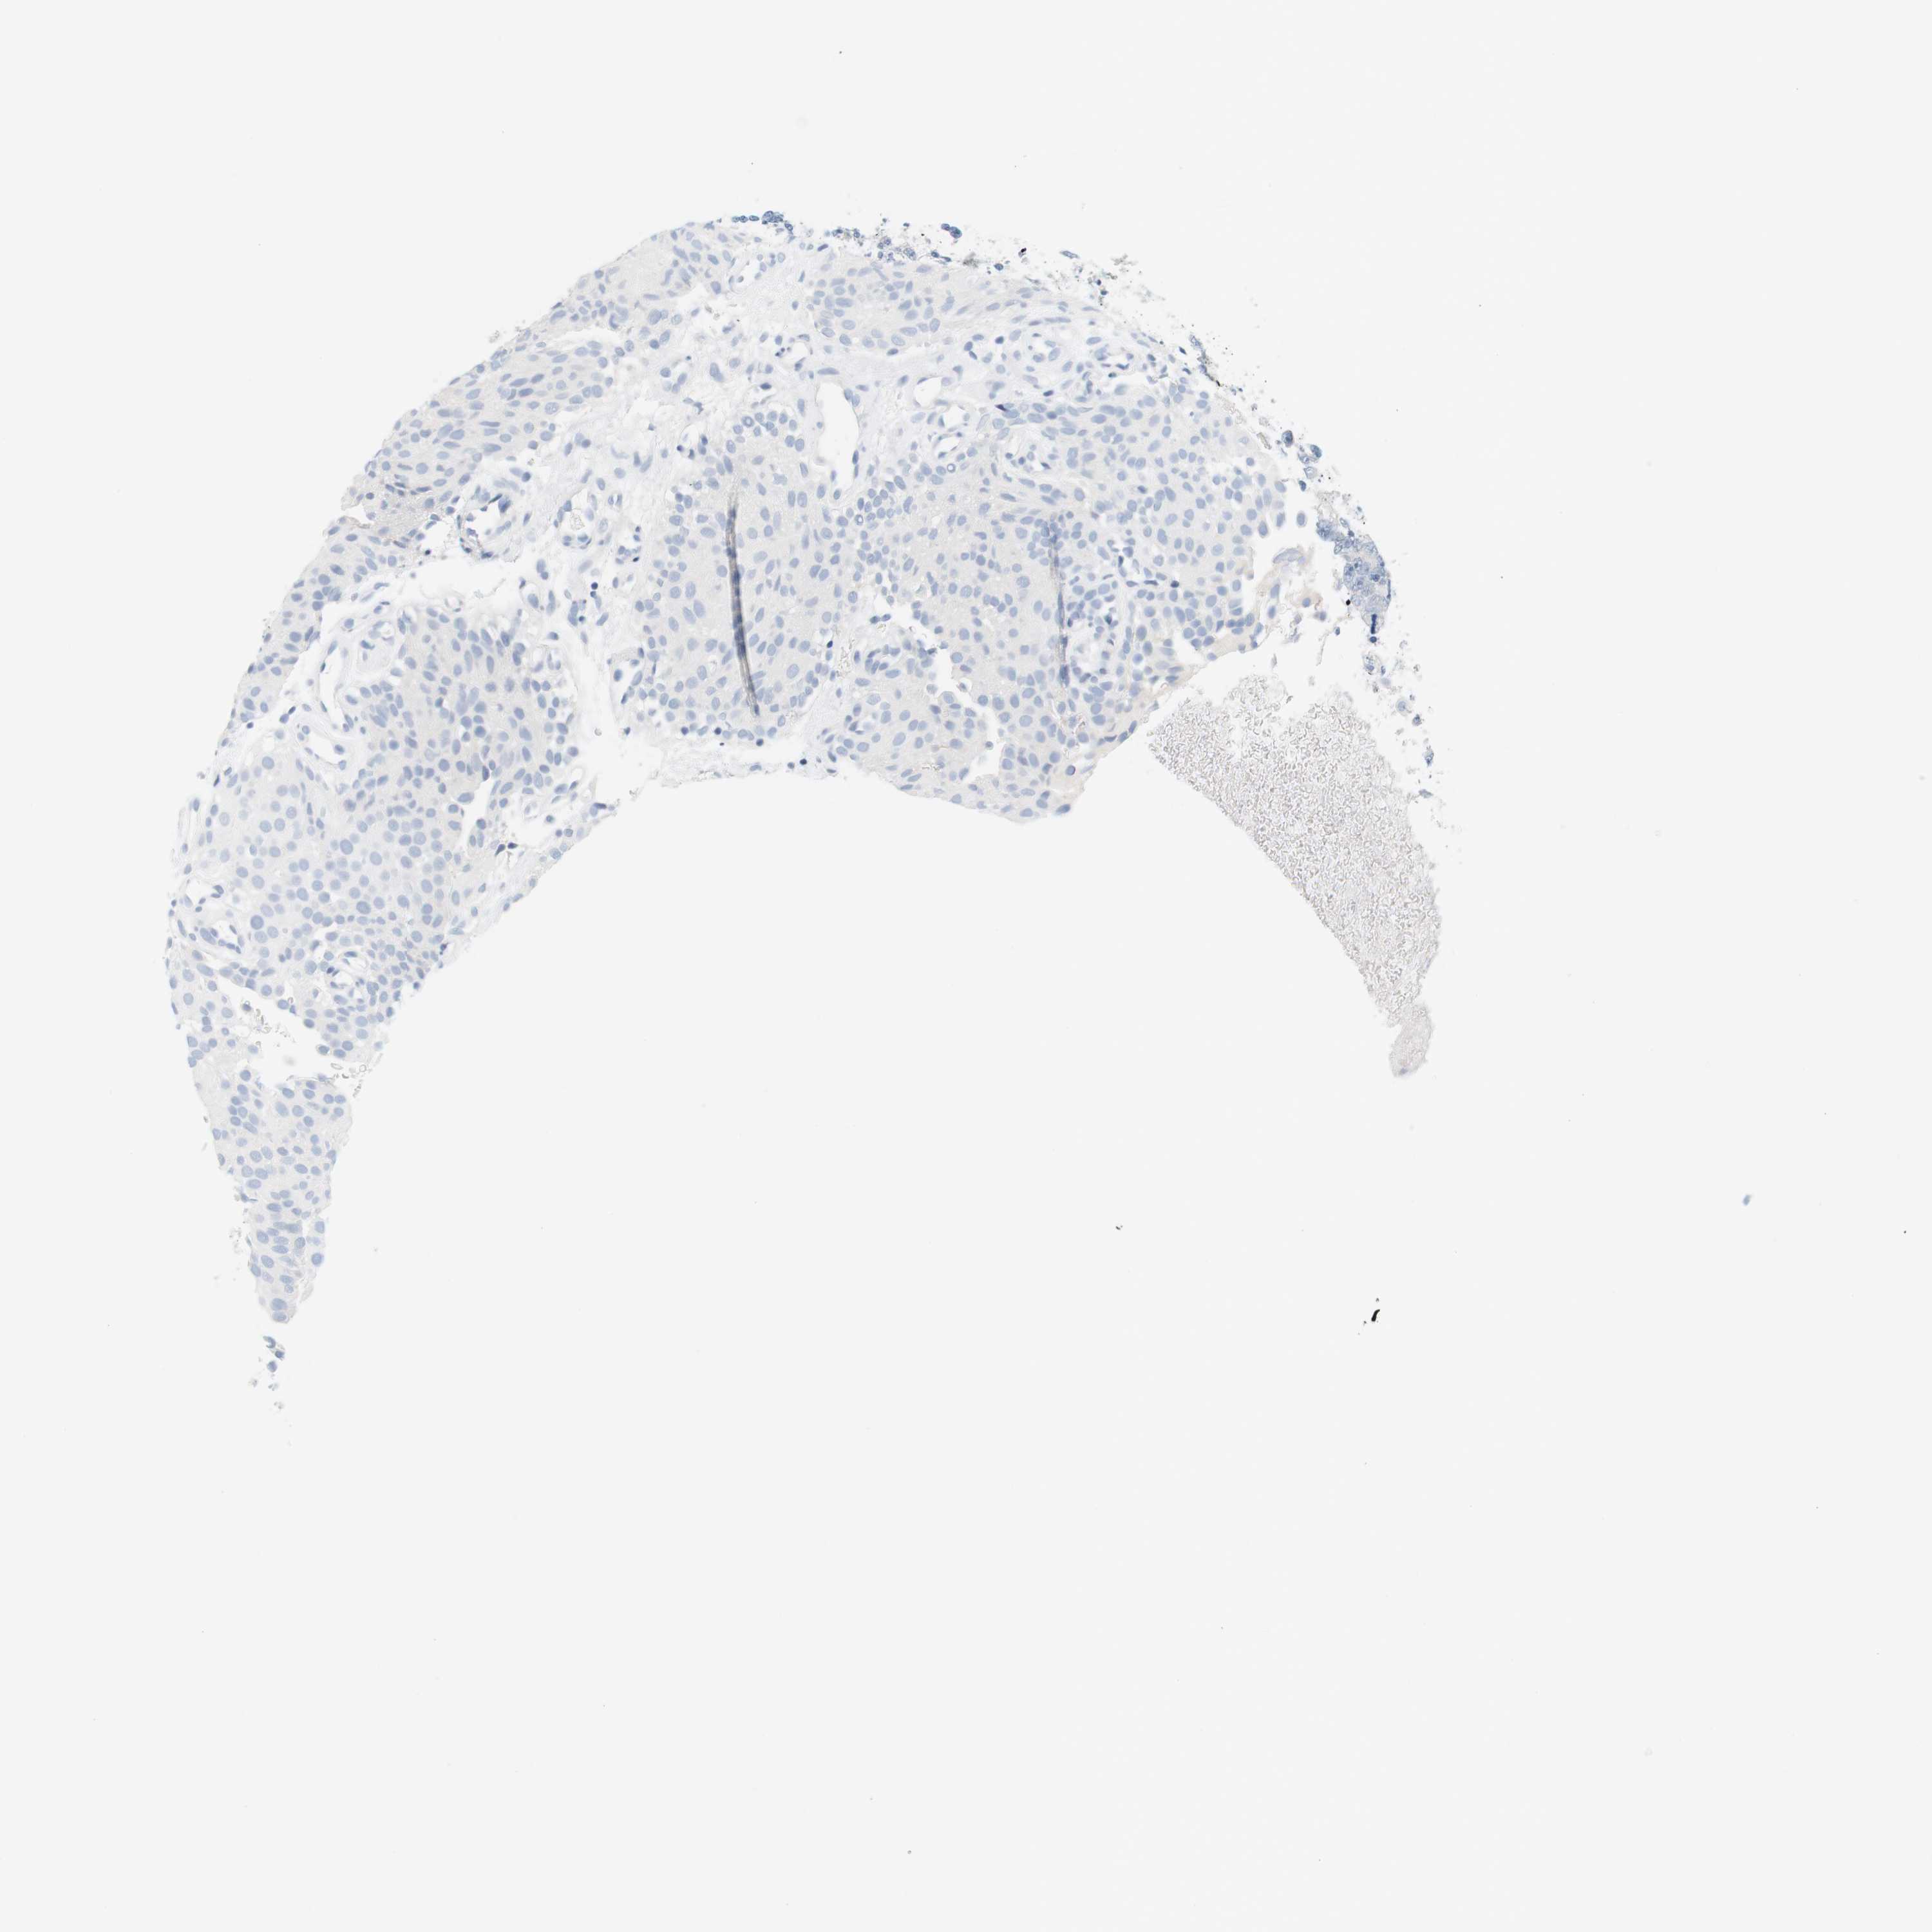

UROTHELIAL CANCER - Protein expressioni

A mouse-over function shows sample information and annotation data. Click on an image to view it in a full screen mode. Samples can be filtered based on level of antibody staining by selecting one or several of the following categories: high, medium, low and not detected. The assay and annotation is described here.

Note that samples used for immunohistochemistry by the Human Protein Atlas do not correspond to samples in the TCGA dataset.

Antibody stainingi

Antibody staining in the annotated cell types in the current human tissue is reported as not detected, low, medium, or high, based on conventional immunohistochemistry profiling in selected tissues. This score is based on the combination of the staining intensity and fraction of stained cells.

Each image is clickable and will lead to virtual microscopy that enables deeper exploration of all samples and also displays staining intensity scores, fraction scores and subcellular localization as well as patient and tissue information for each sample.

Antibody HPA014509

Staining

High

Medium

Low

Not detected

Intensity

Strong

Moderate

Weak

Negative

Quantity

>75%

75%-25%

<25%

None

Location

Nuclear

Cytoplasmic/membranous

Cytoplasmic/membranous,nuclear

Urothelial carcinoma, Low grade

Urothelial carcinoma, High grade